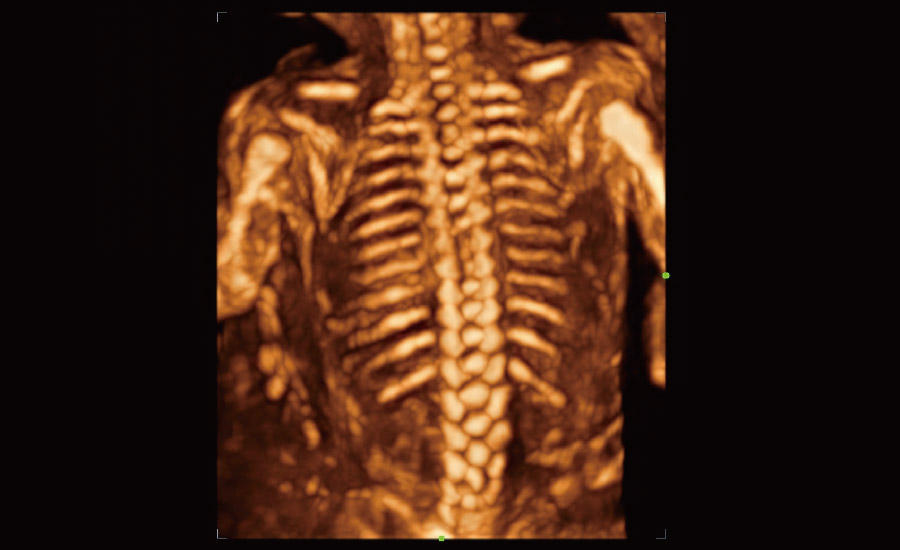

Gra?as Ć revolucionĆ”ria plataforma ZST+, o Nuewa R9 Ć© equipado com tecnologias avan?adas e inovadoras para enfrentar os desafios diagnĆ³sticos na saĆŗde da mulher. Tecnologias revolucionĆ”rias, como a angiografia ultramicroscĆ³pica (UMA), ajudam vocĆŖ a explorar mais microdetalhes e a realidade escondida. Projetado com a inestimĆ”vel sabedoria de especialistas, ele oferece informa??es completas de forma inovadora, que v?o alĆ©m de suas expectativas para diagnĆ³stico com mais confian?a, padroniza??o e eficiĆŖncia frente aos diferentes desafios em ambientes hospitalares exigentes e sobrecarregados.

A tecnologia inovadora elimina as limita??es das tradicionais imagens com Doppler. Com resolu??o espacial e sensibilidade de fluxo ultra-altas, permite a detec??o de perfus?es de fluxos muito sutis e lentos, ampliando assim a aplica??o clĆnica da avalia??o qualitativa e quantitativa do ultrassom no cĆ©rebro fetal, rins, placentas, endomĆ©trios, ovĆ”rios etc.

Por meio da combina??o de algoritmos avan?ados e do conhecimento especĆfico da regi?o, a inovadora solu??o Smart Scene permite a identifica??o automĆ”tica das caracterĆsticas do tecido e fornece diagnĆ³stico especĆfico dos Ć³rg?os com informa??es completas. Com base na identifica??o automĆ”tica de cenĆ”rios, a solu??o realiza n?o apenas a varredura 2D inteligente com configura??es e medidas automĆ”ticas, mas tambĆ©m oferece informa??es 3D abrangentes em todas as etapas, desde a otimiza??o de imagens volumĆ©tricas atĆ© a difĆcil obten??o de planos 2D, e a quantifica??o durante todo o procedimento. Ele ajuda a reduzir em grande parte a dependĆŖncia de habilidades clĆnicas, ao mesmo tempo que aumenta a precis?o, a confian?a e a eficiĆŖncia no diagnĆ³stico.